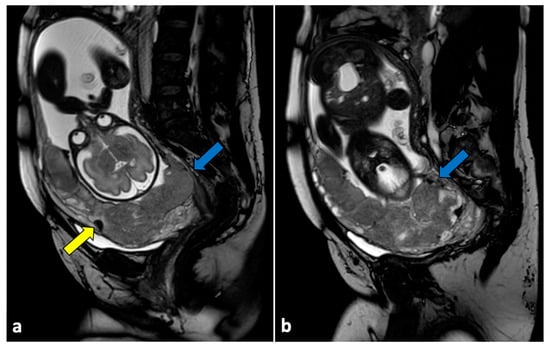

Moreover, MRI can be useful for assessing abnormal placental villous adherences (placenta accreta, increta, and percreta) [89]. Previous caesarean section and placenta location abnormalities (i.e., placenta previa) are the two major risk factors for placenta accreta. In these conditions, the placenta becomes tethered and does not layer smoothly into uniform thickness. Placental border irregularities, uterine bulging, loss of normal uterine contour, and interruption of the junctional zone are frequent MRI findings of placental implantation disorders [90,91,92,93]. T2-weighted dark intraplacental bands, which are greater and more irregular in thickness than normal septa, are also frequently observed. These bands represent a dense region of fibrous tissue that is consistent with placental infarction [94]. Placenta previa is often associated, resulting from the placental tethering that impedes the normal migration of the placenta during gestation (Figure 13).

Figure 13.

Placenta accreta in a 33-year-old patient at 36 weeks of gestation. Sagittal (a,b) T2-weighted MR images show a placenta previa (blue arrows) covering the uterine internal os. Placenta has irregular contours and rounded edges, with a single area of intraplacental dark T2 bands (yellow arrow). No interruptions in the thin hypointense myometrial border are seen. Pathologic examination confirmed the diagnosis of placenta accreta.